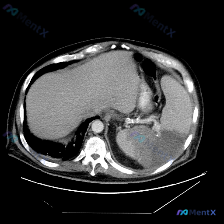

今天整理了一个很有警示意义的影像病例,核心是单张平扫CT下的脾脏病变,想和大家一起梳理下完整的分析思路。 先看影像核心发现 - 定位:上腹部CT软组织窗,左侧脾脏层面 - 关键异常: 1. 脾脏肿大; 2. 脾实质内见大范围、边界尚清晰但密度不均匀的低密度影,形态呈相对弥漫或片状,主要占据后部及部分...